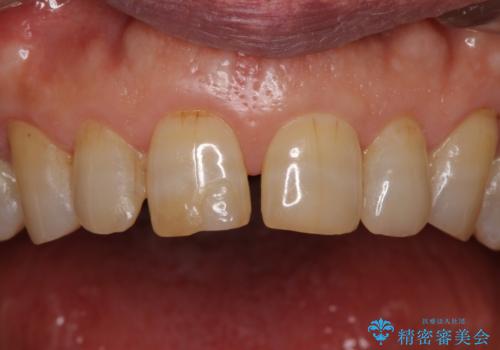

前歯の隙間をオールセラミッククラウンで自然に

- 前歯のすきっ歯を気にして来院された患者様です。

矯正かオールセラミックか、治療の選択がありましたが、ご年齢や色の濃い点を考慮してオールセラミッククラウンにて補綴することとしました。